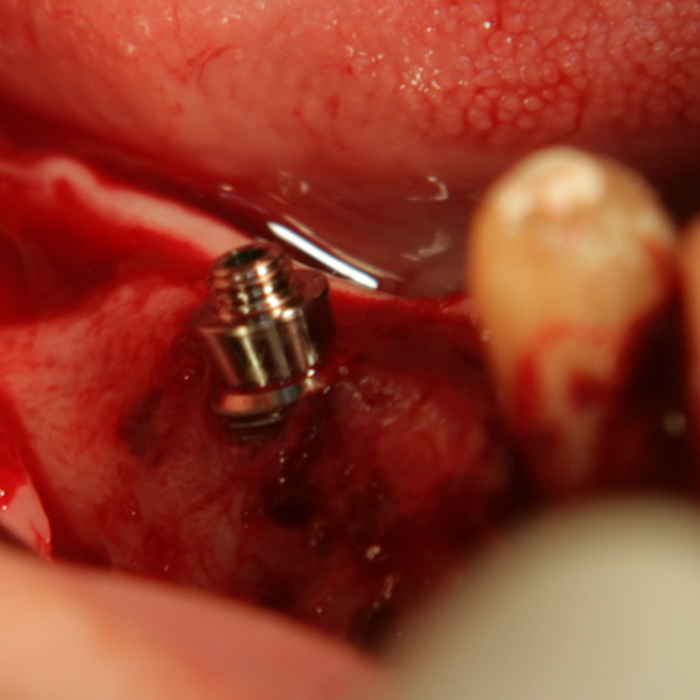

Tent screw - винтове за

фиксиране на титановата мрежа

Около винтовете се поставя костозаместител, добре е да се размеси с

автогенна кост